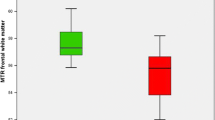

Matched-Pair Analysis of the Periaqueductal Grey

32 controls (mean age, 52.8 ± 9.0 yrs; age range, 30–86 yrs; sex, 72% males) were included in the subgroup analysis and matched with the patient group (age, P = 0.931; sex, P = 0.685; scanner-type, P = 1.000). None of these subjects showed signal changes suggestive of WE, according to both raters. To determine a normal range of values for the maximal width of the PAG on axial FLAIR, an estimated maximum likelihood mean with one SD of 1.45 ± 0.16 mm for the underlying normal distribution was obtained, considering that measurements were rounded to whole numbers (range, 1–4 mm). Consequently, a 95% reference interval of 1.14 to 1.76 mm was established for healthy controls, i.e., 1 to 2 mm after rounding the numbers. Consecutively, a cut-off value of 2.5 mm (i.e., rounded up to 3 mm) was used for pathological enlargement of the PAG. As two patients with visually assessed positive finding of the PAG presented values for the maximal width of rounded 2 mm in the quantitative analysis, both were retrospectively considered as MRI negative for this area, resulting in a final number of n = 20/47 (43%) cases of PAG involvement. However, these two patients had additional thalamic lesions suggestive of WE, thus the final number of MRI positive cases was not affected. The patterns were triangular in 32% (n = 15/47) and circular in 11% (n = 5/47) of cases (Fig. 12).

Autopsy studies have revealed a range from 0.4 to 2.8% of prevalence for WE in the population, strongly suggesting that its diagnosis is greatly underreported [60, 74]. One probable reason might be the fact that only 16 to 33% of subjects present the classical triad of clinical symptoms [3]. Clinicians often face a diagnostic challenge due to the variable expression and broad range of neurological manifestations in a patient cohort that can be difficult to examine clinically, especially during episodes of more excessive alcohol consumption. The notably higher frequency of clinical signs in our cohort (oculomotor deficits, 77%; cognitive impairment/altered mental state, 85%; cerebellar dysfunction, 85%) might be attributed to the retrospective design of this study, which allowed local clinicians, particularly non-neurologists, to reevaluate differential diagnoses after image-guided suspicion of WE. Most interestingly, independent associations between imaging and clinical features could only be made for the presence of changes in the MB and memory impairment in our cohort, but not, as expected, for changes in/around the PAG and the tectal plate with oculomotor deficits, or in cerebellar regions with ataxia. Eventually, all subjects retrospectively met the 2010 EFNS criteria [20]. However, it must be noted that this approach, which is based solely on the presence of a syndromic level, might trade lower specificity for very high sensitivity (e.g., dietary deficits in all chronic alcoholics). Furthermore, our study revealed no clear correlation between the number of positive EFNS criteria and the presence of imaging biomarkers. Excluding the rather unspecific measure of an inadequate supply of essential nutrients, two cases with only signs of cognitive impairment showed clear signal changes on MRI. To date, MRI is recommended to (only) support the diagnosis of WE in both alcoholics and non-alcoholics because it cannot be used to exclude the disease due to its reported rather low sensitivity of 53% [20, 22]. Our study revealed higher rates of positive imaging findings on standard MRI (77%), comparable to the results in studies by Zuccoli et al. (85 and 80%) [14, 30]. This could be explained not only by the analyses being performed by more experienced neuroradiologists, but also by the MRI protocols used in both radiology centers. Moreover, we are the first to describe an approach to manually measure the width of the PAG and set a reference range.

Besides increasing the diagnostic certainty by using the T2 shine-through phenomenon in b = 1000 DWI images or true diffusion restriction in ADC maps, another option to improve detection of hyperintense signal changes might be the implementation of a 3D T2WI and/or 3D FLAIR sequence in standard MRI protocols. However, attention must be paid to its pitfalls, especially in the more commonly involved infratentorial and deep grey matter structures. To overcome these technical hurdles, so-called FLAIR3 images, which can be reconstructed by combining both 3D FLAIR and 3D T2WI, might also enhance the depiction of hyperintense lesions [75]. Flow artifacts related to the cerebrospinal fluid (CSF) in the aqueduct could be a probable reason for the missing suppression of CSF, leading to surrounding small hyperintense signal changes (i.e., in the PAG) in 2D compared to 3D FLAIR images [76]. To account for this, we defined a cut-off value of 2.5 mm width for these hyperintense changes. In our patient cohort, 47% of cases showed 3–4 mm wide FLAIR-hyperintensities in the PAG, making it the second most involved location. Moreover, four patients were rated positive for WE only because these signal changes were detected in the PAG, underlining the importance of analyzing this region in MRI. Whereas in patients with relapsing-remitting multiple sclerosis and clinically isolated syndrome, round-shaped lesions were more predominant than wedge-shaped ones (65 vs. 42%) [77], this study showed lower and opposite frequencies of involvement (11 vs. 32%), the latter possibly due to by the expansion to the neighboring tectum mesencephali. For the use of 3D gradient-echo T1WI, some relevant pitfalls may lead to a higher number of false positive results. Therefore, we recommend using 2D spin-echo CE-T1WI and comparing it with the native sequence. Generally, contrast enhancement in WE is predominantly observed in the MB and thalamus [30].